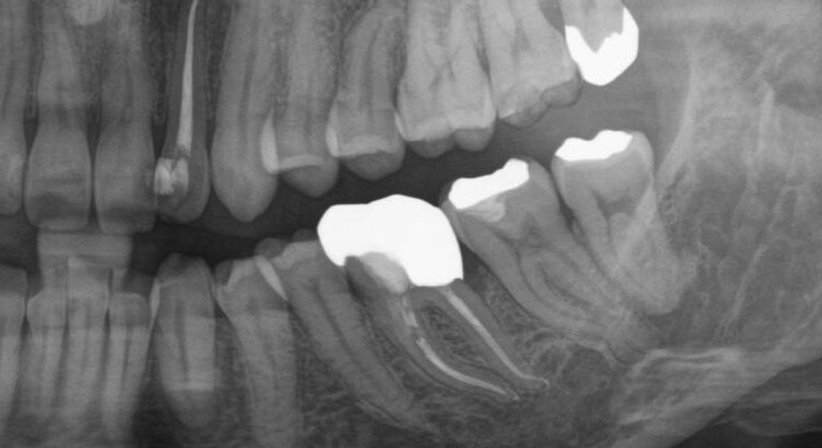

Bei tiefer Karies oder einer Unfallverletzung gelangen Bakterien bis zum lebenden Zahnnerv. Entzündet sich dieser, kommt es zu bohrenden Zahnschmerzen.

Gab es früher nur die Möglichkeit, den betroffenen Zahn zu ziehen, erlaubt die moderne Medizin ihn heute zu erhalten – durch eine Wurzelkanalbehandlung.

Rasante Weiterentwicklungen auf diesem Gebiet machen eine laufende Weiterbildung nötig; feinste Präzisionsarbeit mit Lupe und Mikroskop erlaubt es dafür, selbst stark infizierte Zähne zu retten.